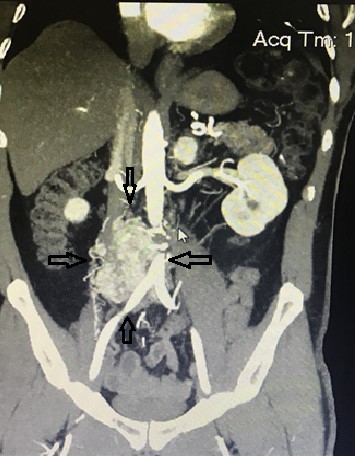

Հիվանդը /62տ./ դիմել է «Աստղիկ» ԲԿ՝ գանգատվելով բարձր զարկերակային ճնշումից(220/120-սահմաններում), որը վերջին 6 տարիների ընթացքում ընդհանրապես չի ենթարկվել դեղորայքային բուժման: Հիվանդի մոտ նաև առկա էր շաքարային դիաբետ, և միայն ինսուլինի բարձր չափաբաժինների ներարկումները հնարավորություն էին տալիս կարգավորել գլյուկոզայի մակարդակն արյան մեջ: Բժշկական կենտրոնում կատարված կոնտրաստային ԿՏ-անգիոգրաֆիան հայտնաբերեց վերը նկարագրված Ցուկերկանդլի ուռուցքը: Վերջինիս ախտորոշումը հաստատվեց համապատասխան հորմոնային անալիզներով: Փոխանցում է Աստղիկ ԲԿ-ի կայքը:

Համապատասխան մասնագիտացված նախավիրահատական պատրաստումից հետո կատարվել է ուռուցքի հեռացում՝ լապարոտոմիկ եղանակով Էնդոկրին վիրաբուժության ծառայության ղեկավար Արմեն Վարժապետյանի կողմից: Հետվիրահատական շրջանում զարկերակային ճնշումը և գլյուկոզայի մակարդակն արյան մեջ նորմալացել են համապատասխանորեն՝ առանց հակաճնշումային դեղամիջոցների և ինսուլինի: